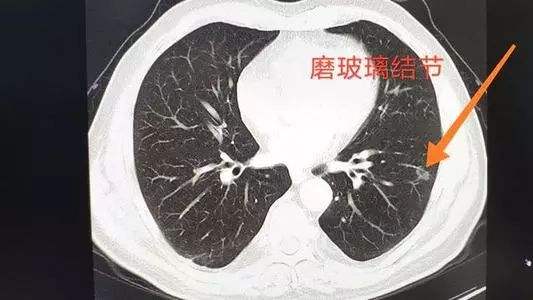

“临床上,不少患者的肺癌是由磨玻璃结节发展而来,因此很多人看到‘磨玻璃结节’几个字就非常紧张。”江苏省肿瘤医院胸外科主任医师李明表示,磨玻璃结节中,确实有10%左右可能会恶化,但大多数磨玻璃结节是安全的。含有实性成分的磨玻璃结节一定要小心,半磨半实结节的恶性概率最高。磨玻璃结节是否高危,需由专业医生进行诊断。